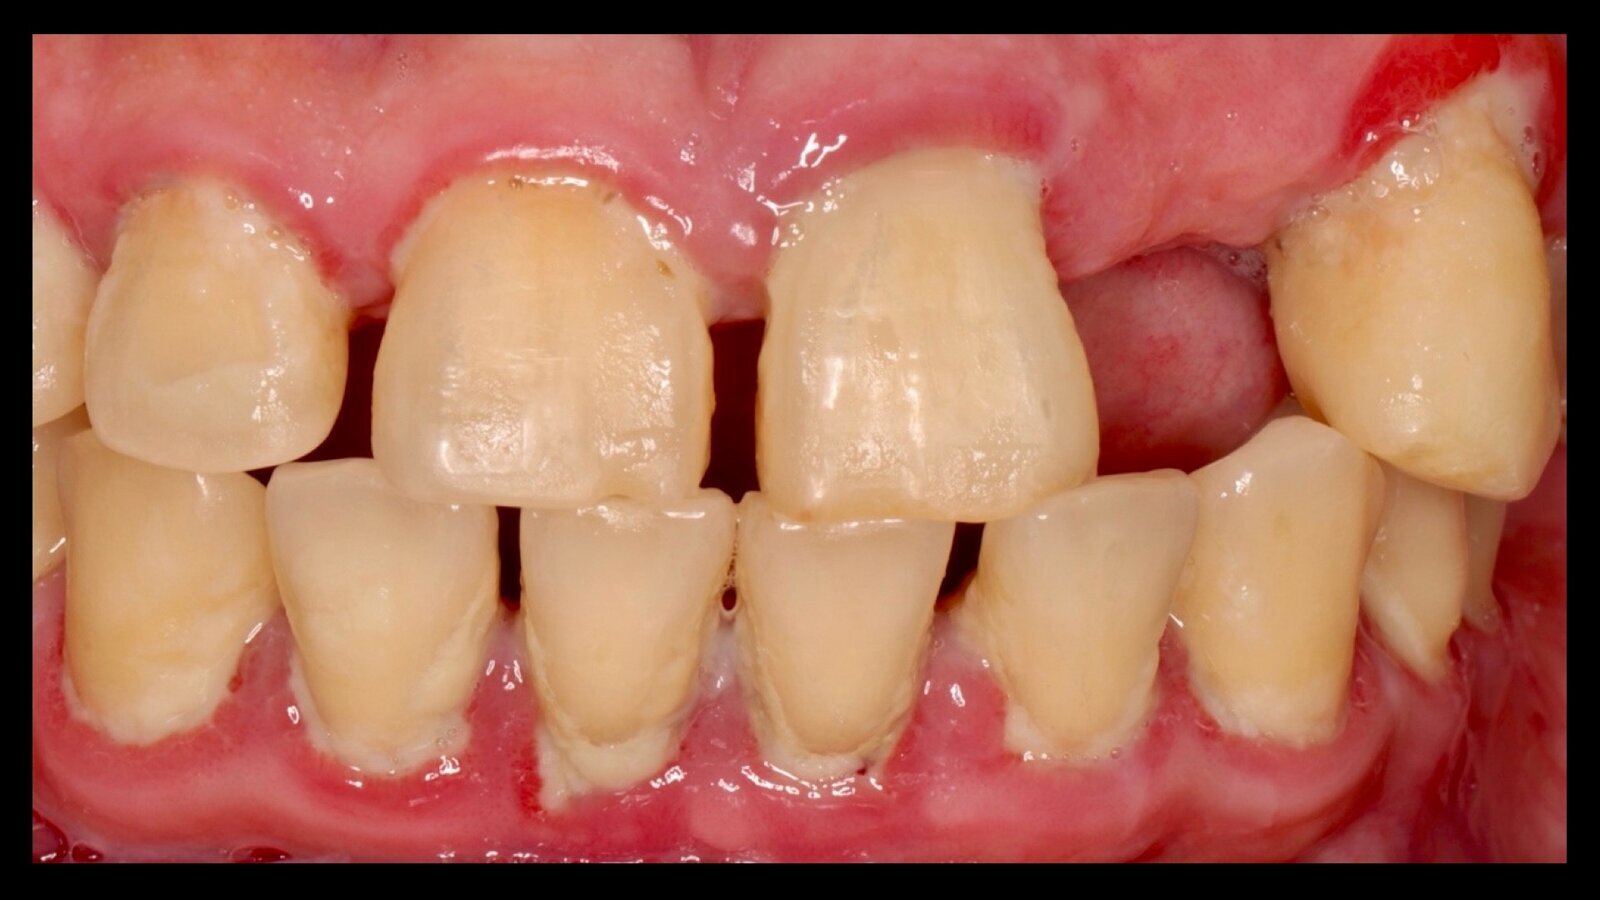

Paciente con xerostomía que toma quetiapina y alprazolam de manera crónica.

También se ha informado una reducción en la tasa de flujo salival en casos relacionados con diversos medicamentos, entre los que se incluyen: alendronato (antiresortivo), bendroflumetiazida (diurético tiazídico), clonidina (antihipertensivo), furosemida (diurético). Además, medicamentos como opioides (codeína, tramadol), antihistamínicos (cetirizina), antieméticos (droperidol, domperidona), antiparkinsonianos, ansiolíticos (alprazolam, diazepam), antiespasmódicos (diciclomina) y relajantes musculares (tizanidina) también pueden influir en la función de las glándulas salivares, lo que podría resultar en una reducción del flujo salival.